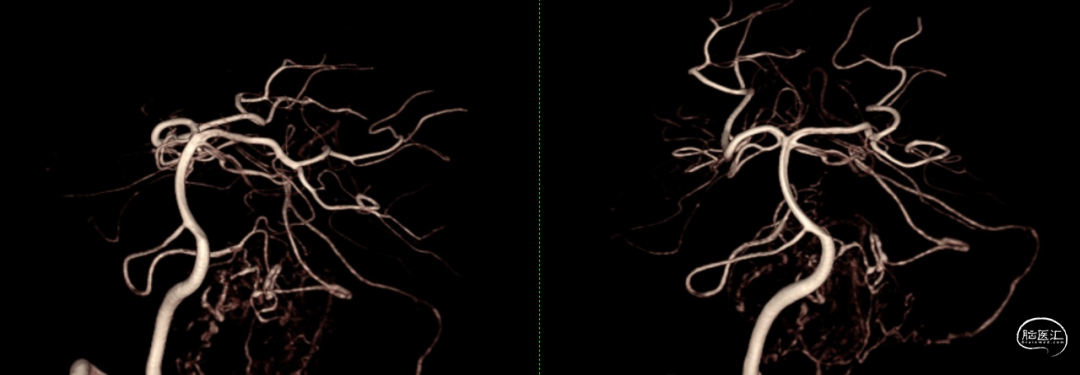

DSA:显示肿瘤主要由PICA及SCA分支供血,单支向上向窦汇引流。